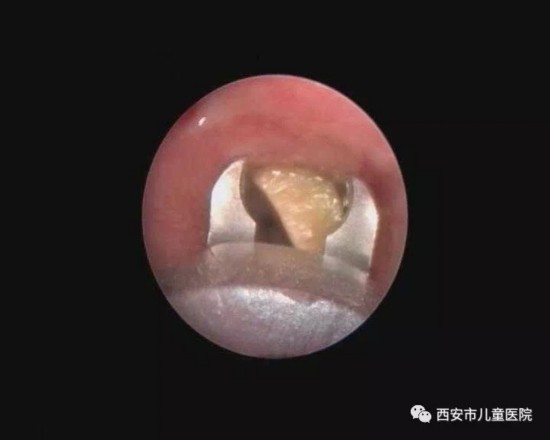

春节西安儿童医院接诊21例气管异物 别给5岁以